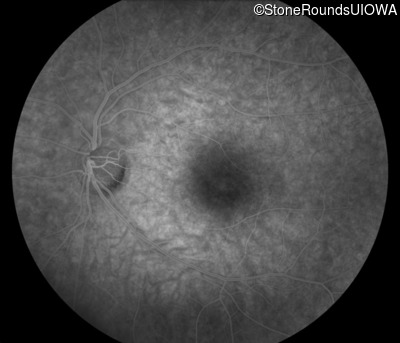

Infrared Fundus Photograph - Right - 20/20 -1

Exemplar